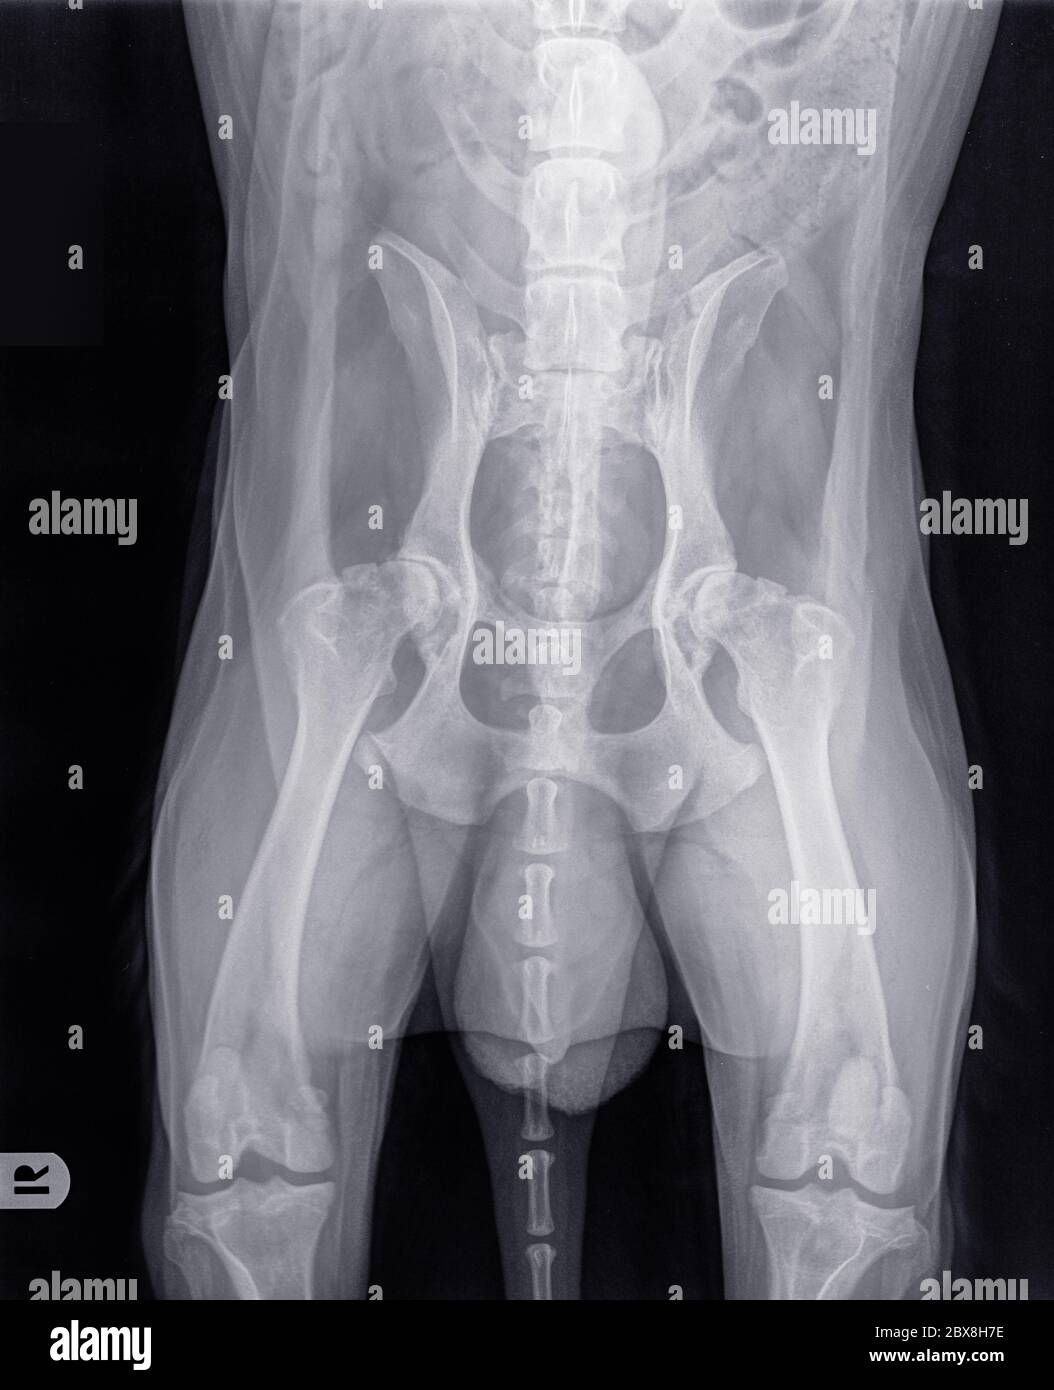

From www.shutterstock.com

Digital Xray Dog Severe Hip Dysplasia Stockfoto 1446347339 Shutterstock Hip Dysplasia In Older Dogs hip dysplasia is a multifactorial abnormal development of the coxofemoral joint in dogs that is characterized by joint laxity and. Find out the signs, risk factors, diagnosis, treatment options, and life expectancy for affected dogs. hip dysplasia is a common inherited disease in dogs. learn about hip dysplasia in dogs, a common developmental condition that affects large. Hip Dysplasia In Older Dogs.